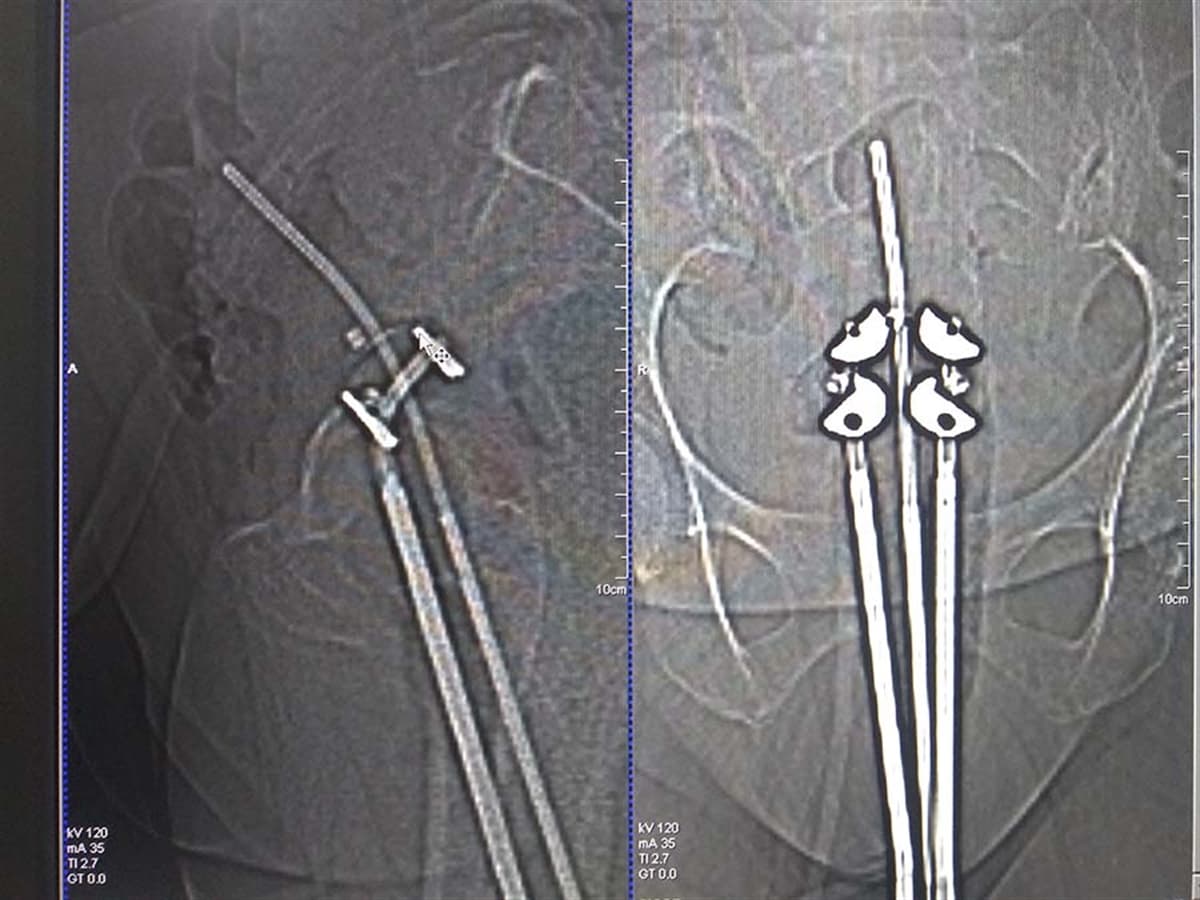

Brakiterapi, kanserli hücrelerin bulunduğu yere doğrudan ışın verebilmek için vücudun içine küçük radyoaktif kaynakların yerleştirilmesidir. Bu yöntemle küçük volüme en yüksek doz verilirken normal dokular korunabilmektedir. Genellikle dışarıdan uygulanan tedaviye ek olarak uygulanır. Tedavinin temel amacı, etraftaki normal dokuları radyasyondan koruyarak tümörlü bölgeye yüksek dozlarda radyoterapi verebilmektir. Radyoaktif kaynakların özel aplikatörler yardımıyla, doğal bir vücut boşluğuna, ışınlanacak doku ile temas edecek şekilde yerleştirilmesi ile gerçekleştirilir. En yaygın kullanım alanı bayanlarda rahim ve rahim ağzı kanserleridir. Çoğunlukla önce harici radyoterapi uygulanır, takiben hastalık bölgesinde dozu artırabilmek için brakiterapiye geçilir. Bu amaçla en sık kullanılan radyoaktif kaynak İridyum-192 elementidir. Kaynak uygulayıcı cihazın içinde muhafaza edilir. Cihaz özel kataterler yardımıyla aplikatörlere bağlıdır. Aplikatörler radyoaktif değildirler. Bunlar genellikle ağrılı olmayan bir işlemle örneğin sadece vajinaya ya da vajina ile birlikte rahim içine yerleştirilir. Bazı hastalar için uygulamadan önce bir sakinleştirici enjeksiyonu gerekebilir. Çok nadiren genel ve spinal anesteziye gerek duyulur. Aplikatörler yerleştirildikten sonra, doğru pozisyonda olup olmadıklarının kontrolü için röntgen filmi alınır, gerekirse düzeltme yapılır. Tedavi başlamadan önce, bu bölgeye yakın kritik organlardan mesane (idrar torbası) ve rektuma (kalın barsak ucu) özel aletler yerleştirilerek bu organların alacağı dozlar bir monitör yardımıyla görüntülenir. Aplikatörler yerleştirildikten sonra personel oda dışına çıkar, radyoaktif kaynaklar dışarıdan otomatik olarak yerleştirilir. Tedavi bitiminde de otomatik olarak geri çekilir. Tedavi çoğu merkezde ortalama 5-20 dakika sürer ve hasta bu süre boyunca mümkün olduğunca hareket etmemeye çalışmalıdır. Çünkü aplikatörler yerinden oynayabilir ve bu doz dağılımını bozar. Tedavi için önceden belirlenen süre tamamlandığında hasta evine dönebilir. Bu işlem genellikle birer hafta ara ile birkaç kez tekrarlanacaktır. İşlem sonunda radyoaktif kaynak kapatılıp, aplikatörler çıkartıldığında, tüm radyoaktif belirtiler ortadan kalkar. İnsan ilişkilerini bu korku nedeniyle sınırlamasına kesinlikle gerek yoktur.